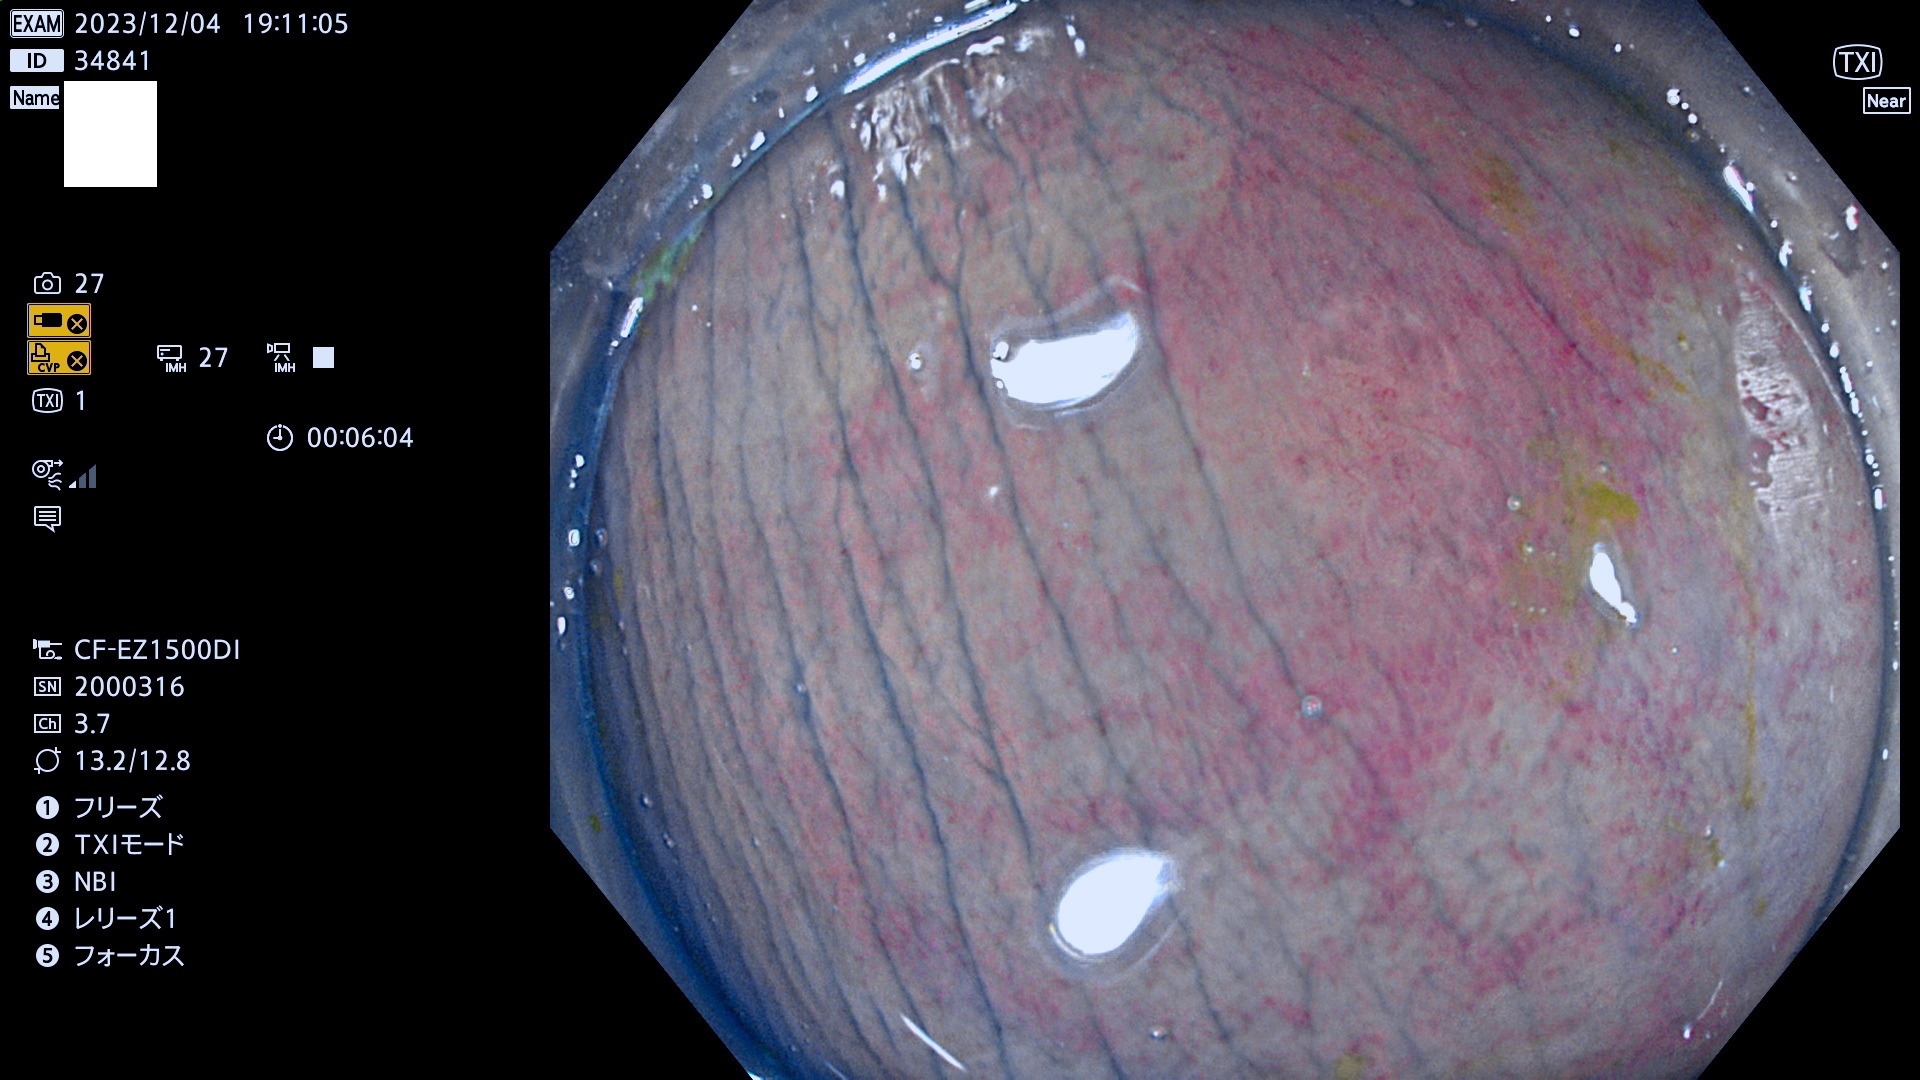

表面型腺腫(Flat Adenoma)の中で、完全に平坦な物をUb、陥凹している物をUcと呼びます。平坦隆起型(Ua)よりも、発見が難しく危険な病変です。このタイプは「内視鏡後・大腸癌の重要犯人」であり、この発見率は「腺腫発見率」よりも、重要な意味があります。

毎週の検査(木・金・土・日)に発見されたUb、Uc型・腺腫を、その週の日曜の夜にUPし1週間、提示します。

抽出の対象期間 2023年11月30日(木)〜12月4(月)の5日間(60件の検査)6件